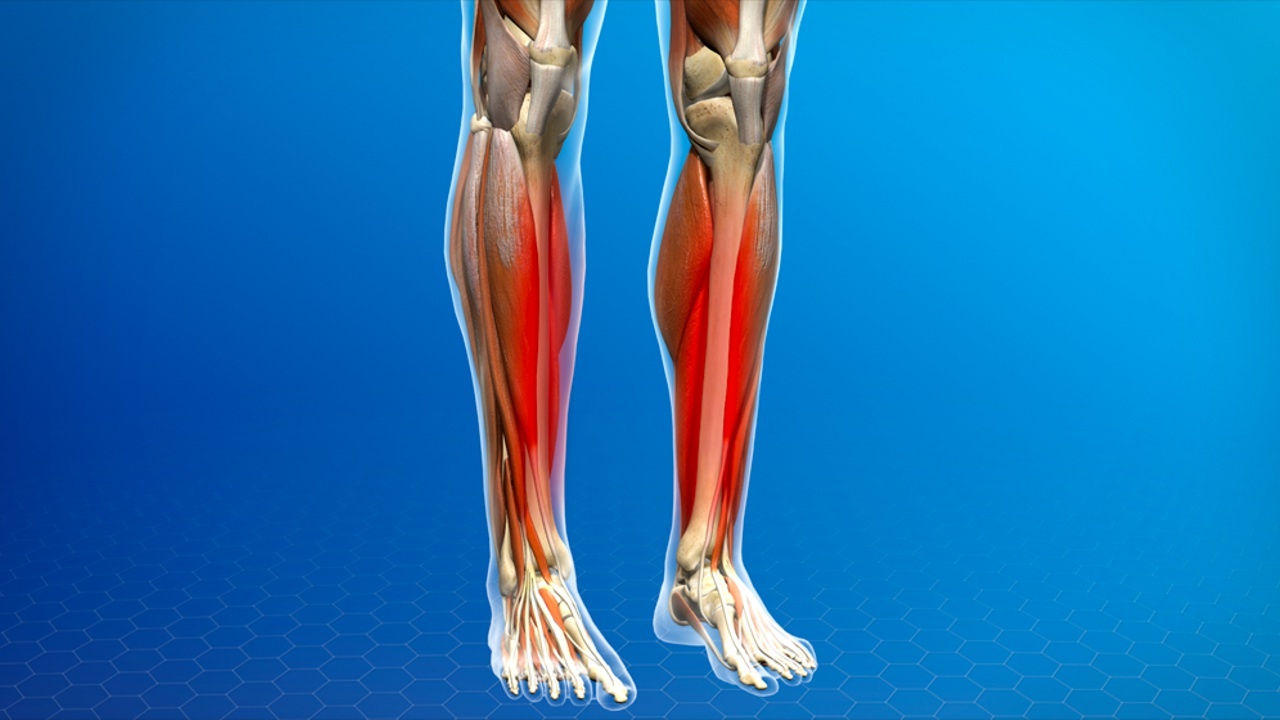

Shin splints, ook wel bekend als "scheenbeenirritatie", is een veelvoorkomende blessure onder hardlopers, dansers en atleten. Het veroorzaakt pijn langs het scheenbeen, het bot aan de voorkant van je onderbeen, en kan je dagelijkse activiteiten flink verstoren. Gelukkig zijn er verschillende stappen die je kunt nemen om shin splints te behandelen en te voorkomen.

Shin splints, ook wel bekend als "scheenbeenirritatie", is een veelvoorkomende blessure onder hardlopers, dansers en atleten. Het veroorzaakt pijn langs het scheenbeen, het bot aan de voorkant van je onderbeen, en kan je dagelijkse activiteiten flink verstoren. Gelukkig zijn er verschillende stappen die je kunt nemen om shin splints te behandelen en te voorkomen.

Voordat je kunt begrijpen hoe je shin splints kunt behandelen, is het belangrijk om te weten hoe deze blessure ontstaat. De pijn wordt meestal veroorzaakt door overbelasting van de spieren, pezen en botweefsel rond je scheenbeen. Vaak gebeurt dit als je te snel te veel gaat trainen, vooral op harde ondergronden. Andere factoren zijn een slechte looptechniek, verkeerde schoenen of een zwakke core en onderbeenspieren.